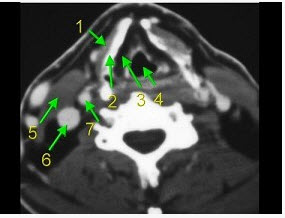

下面是一颈部CT图,其中结构标志不正确的是()。

A、2为甲状软骨

B、3为声门旁隙

C、5为胸锁乳突肌

D、6为颈内动脉

E、7为颈内动脉

D